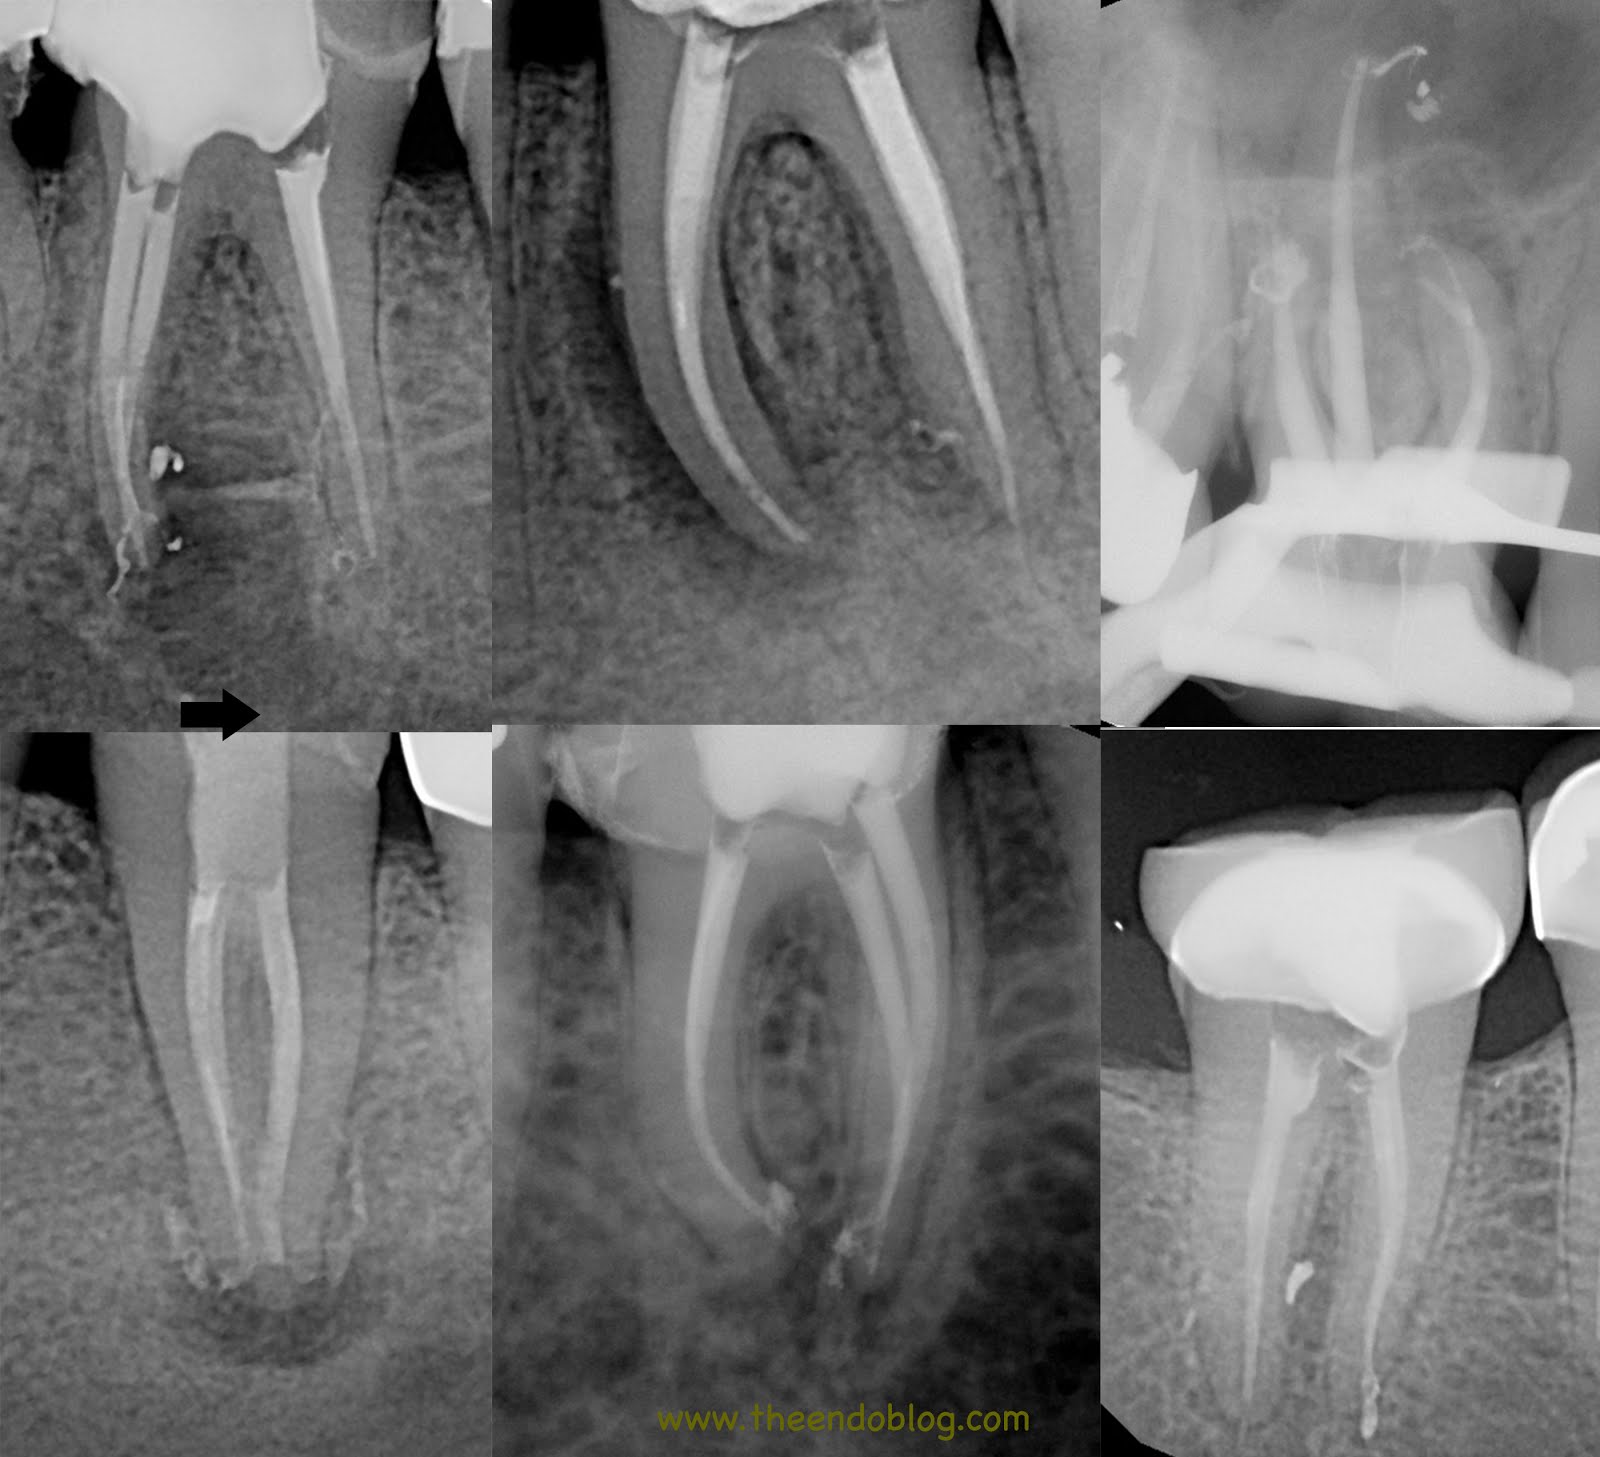

From www.theendoblog.com

The Endo Blog The Buzz About Endodontic Irrigation Method Of Endodontic Irrigation The purpose of study is to analyze and compare the different irrigation methods present in the field of endodontics and to determine the optimum method for a successful root. Activated irrigation is a potentially important method to counteract these problems, with an aim of chemically and mechanically. This expert consensus aims to establish the clinical operation guidelines for root canal. Method Of Endodontic Irrigation.